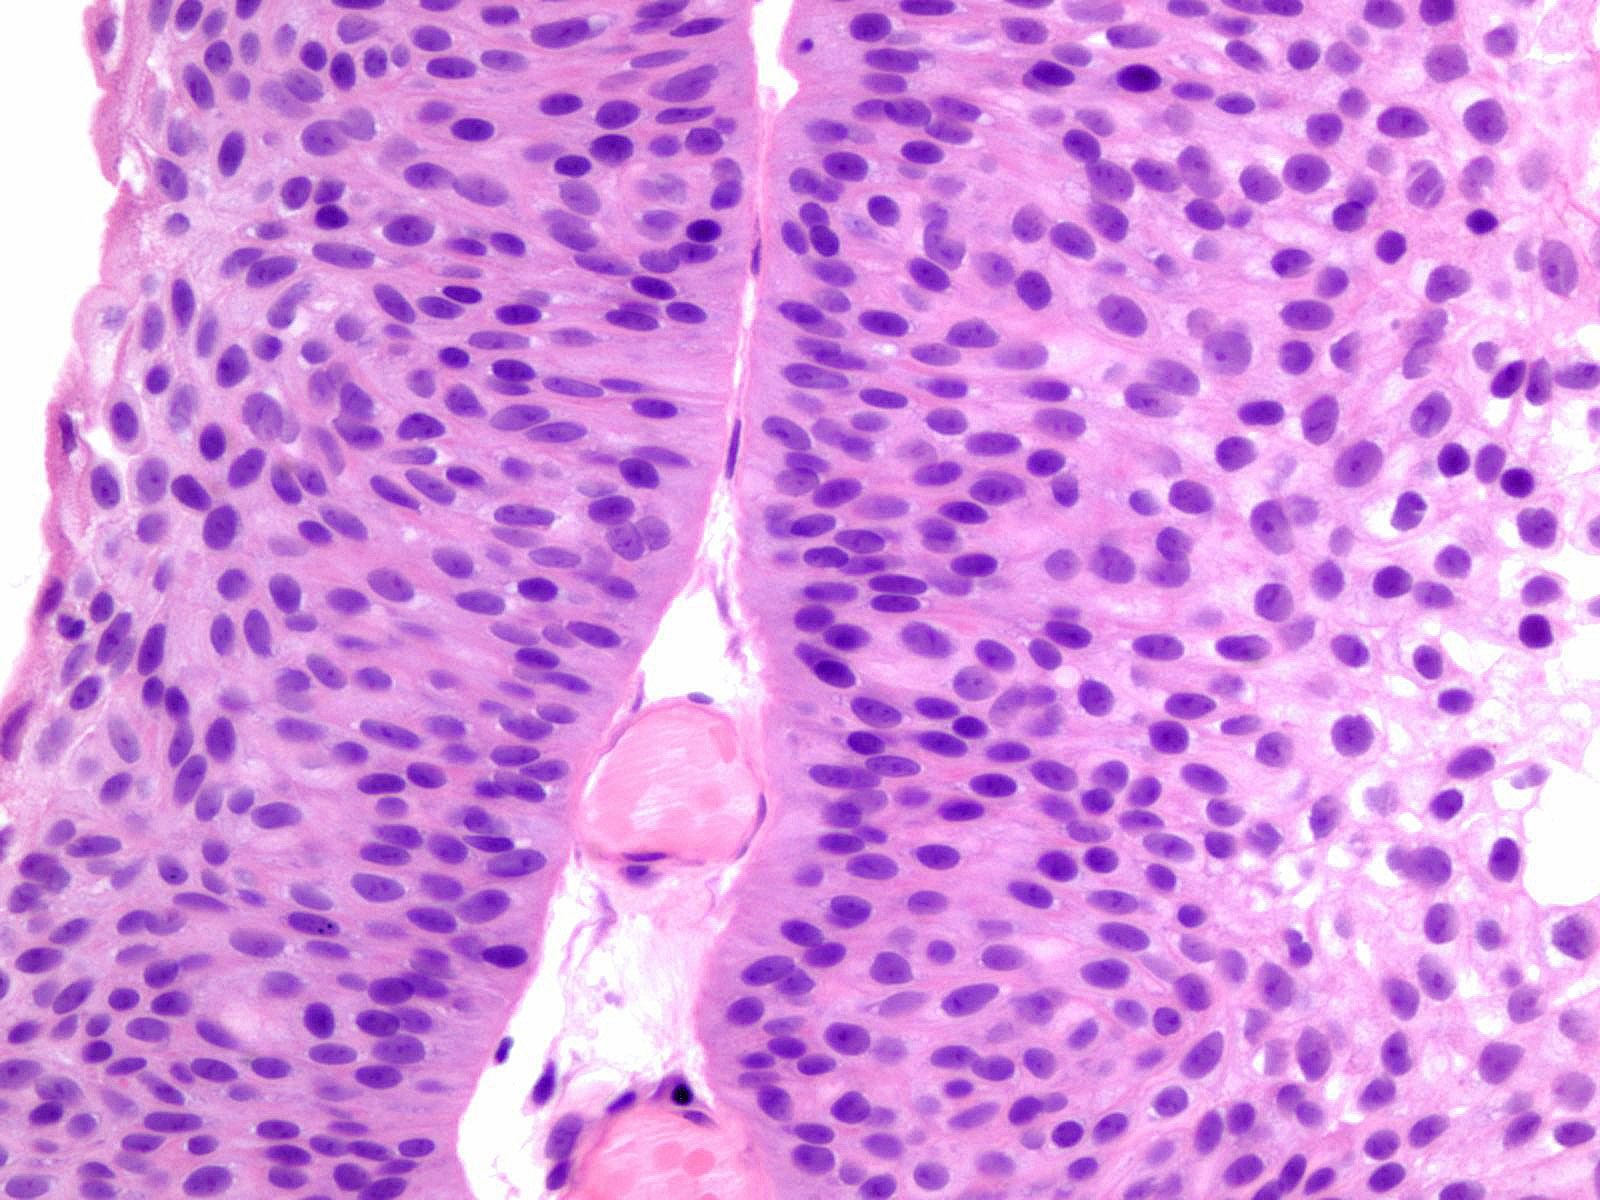

Bladder Papillary Lesions

Case ID: 121